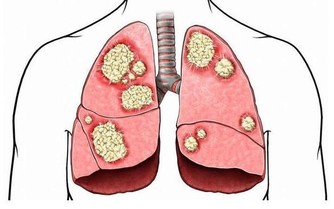

在糖尿病友中最常見也最容易被忽視的是「阻塞性睡眠呼吸障礙低通氣綜合徵」(OSAHS),這類患者貌似睡得很好、鼾聲如雷,實則未能真正地進入睡眠。目前,在全國范圍內,2型糖尿病患者的OSAHS患病率在23%~75%;研究發現,我國住院2型糖友中OSAHS的患病率接近70%,另有半數以上糖尿病友有其他類型的睡眠障礙,如失眠和早醒等。

如出現打鼾等症狀,要及時檢測甲狀腺功能,治療由於甲狀腺功能減退所引起或加重的OSAHS。

若OSAHS是由於黏膜組織肥厚等引起的,也可選擇手術矯正治療。